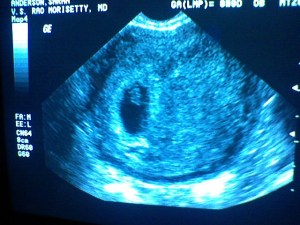

So it’s finally public….we are expecting a NEW BABY! February 21st, 2008. We are about 8 weeks in right now, so it’ll be another 12 before we can announce the gender. We are very excited! We found out on Father’s Day (which was an awesome present), but wanted to wait until the first ultrasound to announce it.